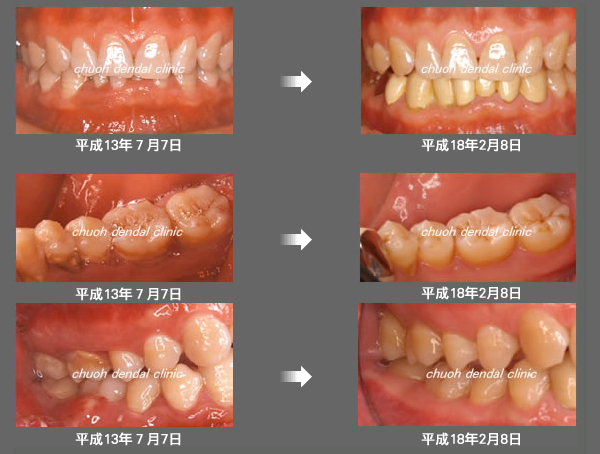

治療の特徴(患者T様)

平成13年7月7日 右下第一大臼歯頬側に膿瘍形成 著しい腫れ形成 著しい腫れ

- 男性33歳

- 平成14年11月9日 どうしても抜きたくないということで歯周外科処置する。

- その後H16から1~2カ月おきにメインテナンス。

- 平成16年6月11日 歯周治療により骨が出来てきています。

口の中から細菌を除去し、良好な環境を維持していくことによって歯周組織である歯槽骨や歯肉、歯根膜は生き生きとよみがえってきます。継続は力なりと申しますが根気良く治療を続けることで健康が回復し維持されます。

| 治療期間 | 4年7カ月 |